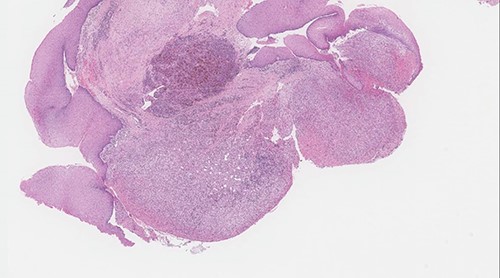

The post-operative course was uneventful, and the patient was discharged the same day with analgesics and anti-reflux medications. The patient was given appointment for follow in otolaryngology clinic one week after discharge for pathology review and reassessment. Pathology report revealed lobular capillary hemangioma with no evidence of malignancy. Histologic sections showed polypoidal squamous mucosa with associated superficial ulceration and fibrinoid necrosis (Figs 7 and 8). Submucosally, there was proliferation of small blood vessels arranged as lobules with surrounding granulation tissue and chronic inflammatory cells (Fig. 9). The endothelial cells were bland, spindled and lack dysplastic features. No atypical mitotic figures were identified. The squamous epithelium adjacent to the ulceration showed hyperplastic changes. After 2 months patient was re-evaluated again and reported improvement of his symptoms. Examination showed normal larynx with no signs of recurrence.

Polypoid squamous mucosa with ulceration and peripheral hyperplastic changes (original magnification: X40, H&E stain).

Surface ulceration with prominent fibrinoid necrosis (original magnification: X40, H&E stain).